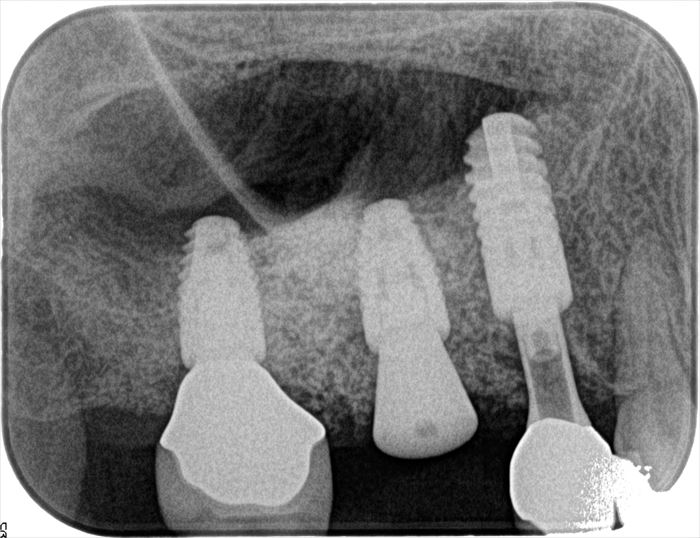

画像左端の右上第二大臼歯部分のインプラント埋入オペ時のデンタルレントゲン写真です。

丸印が本日撤去するインプラントです。

インプラントネック部分が骨吸収を起こしています。